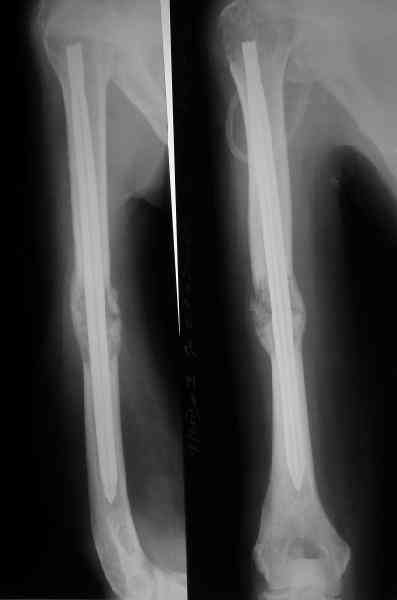

Сегодня сделали, Fixion диаметром 7,4 мм. Обе пперации продолжались по 7 мин. Картинки в приложении. Наркоз был диприваном, на спонтанном дыхании. По крайней мере, пока довольны хотя бы анестезиологи, похоже, не верили, что управимся меньше, чем за час ;-)

Гвоздик 7,4 расширяется до 11 мм. Не маловато ли, судя по снимкам?

7,4 мм, рсширяющийся до 11 мм, в принципе, достаточно для плеча. Хотя мне тоже показалось, что можно было бы и потолще. Вообще есть и следующий диаметр, 8,5 мм, расширяющийся до 13,5 мм, но его в наличии на сегодня не было.